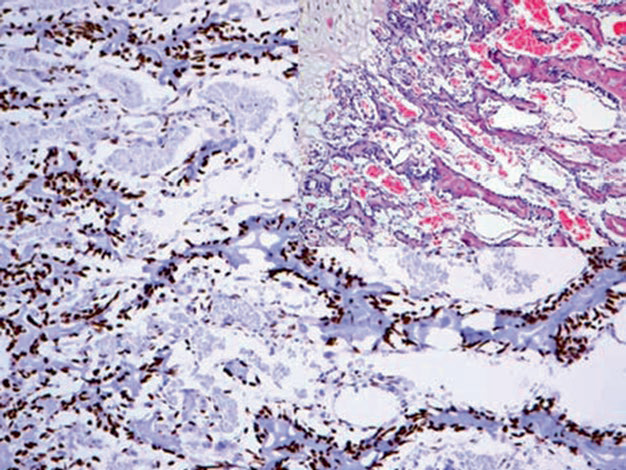

特异AT序列结合蛋白2(Special AT-Rich Sequence-Binding Protein 2,SATB-2)是一种与骨母细胞分化有关的转录因子和DNA结合核蛋白,正常情况下表达于骨母细胞、脑、肝、肾和结直肠上皮(本系列文章前已有述)。SATB-2在骨及骨外的骨肉瘤中,均可表达于肿瘤性骨母细胞。

图1. 胎儿骨组织切片,骨母细胞强阳性表达SATB-2。